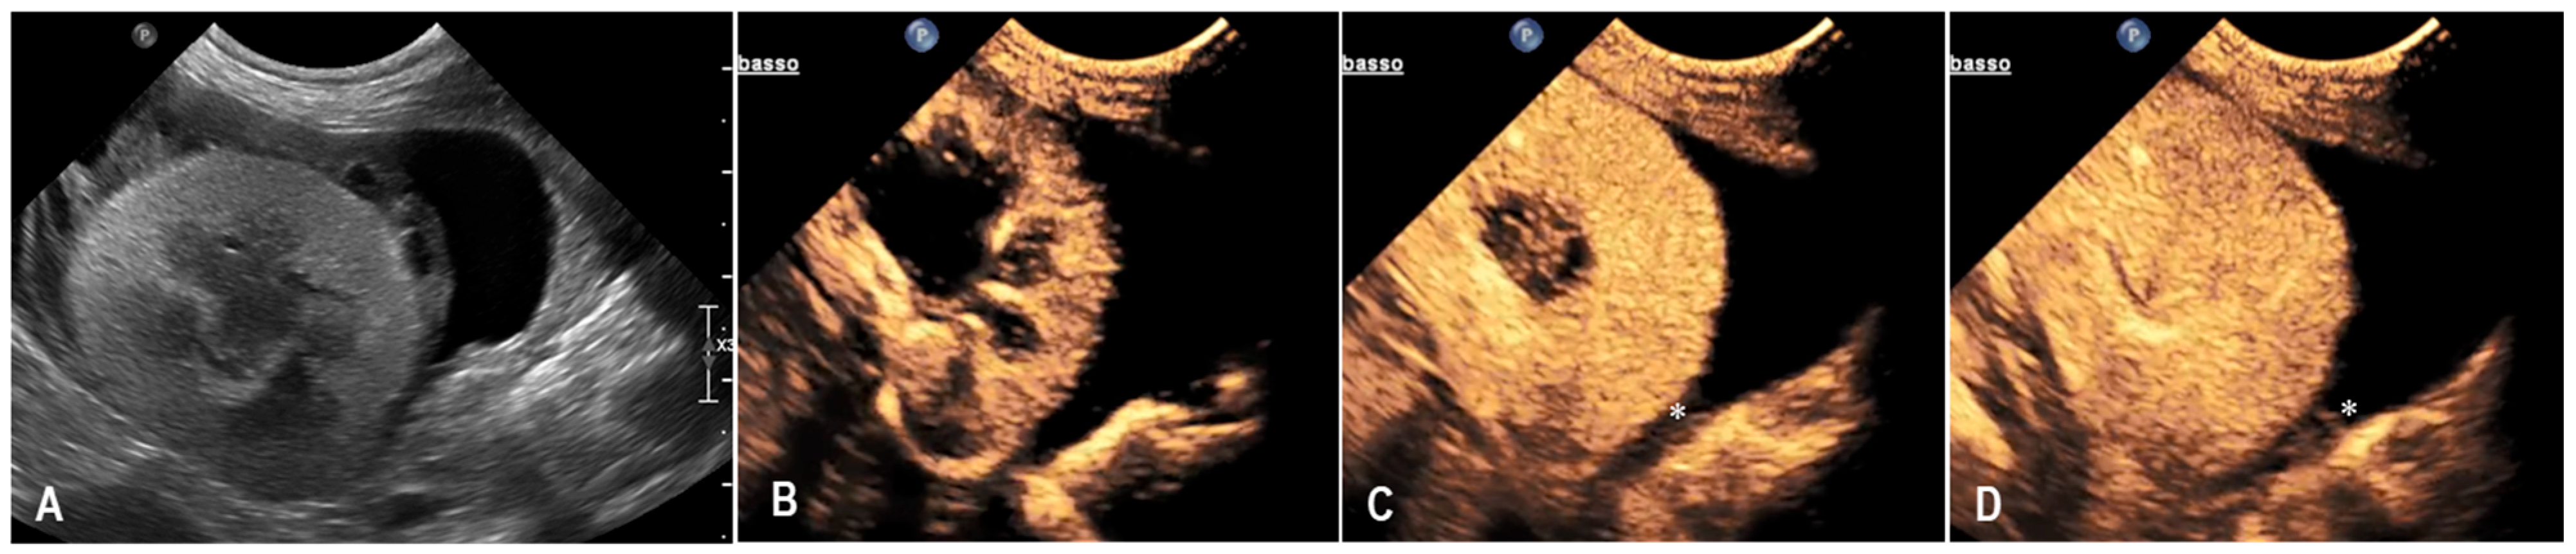

3.3. Case 3